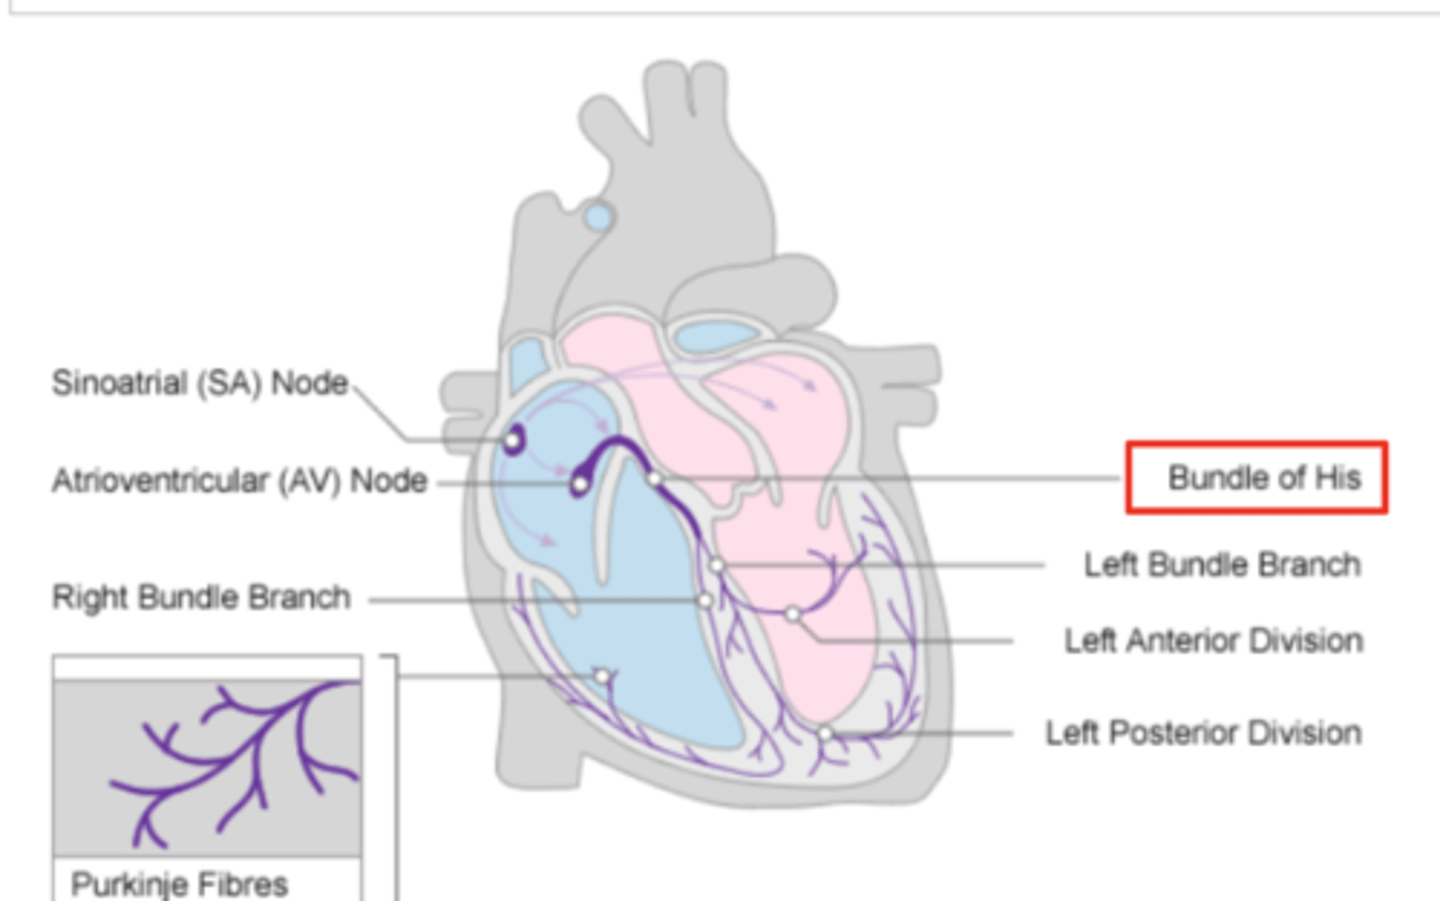

AV node is followed by?

Bundle of Hiss that divides into two branches

Where does Bundle of Hiss ends?

Purkninje fibers

Describe the propagation of waves in the conduction system ?

. SA node sends the initial wave

Passes through the walls of the atria

. Ends at the AV node in the AV septum

. Travels along the Bundle of His

. Reaches Purkinje fibers in the walls of the ventricles

What role does the moderator band play in the conduction system?

Allows the wave to reach the papillary muscles, inducing their contraction simultaneously with that of the ventricles.

REMEMBER: PAPILLARY MUSCLES ACT THROUGH THE CHORDAE TENDINAE TO CONTROL THE TRICUSPID AND MITRAL VALVES.

What is the significance of the Bundle of His in heart conduction?

Branching to the right and left to ensure coordinated contraction of the ventricles.

What are the Purkinje fibers, and what is their function?

specialized conductive fibers in the walls of the ventricles that

facilitate rapid transmission of electrical impulses,

ensuring efficient and synchronized ventricular contraction.

How does the AV node contribute to heart rhythm?